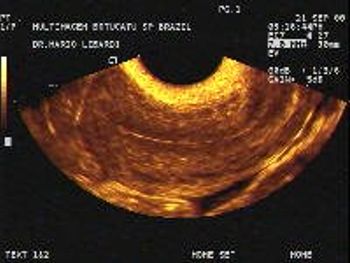

Gynecology Images: Normal Abnormal Obstetric Images: 1st Trimester: Normal Abnormal 2nd Trimester: Normal Abnormal 3rd Trimester: Normal Abnormal Medical Professionals: Upload Your Here Obstetric Images: 3rd Trimester: Normal Normal Thymus - Albana Cerekja Fetal urethra at 31 weeks: just before micturition - Albana Cerekja Normal Female: 4D still image - Effendi Mansoor Monolateral double renal artery,: Normal variant kidney artery supply - Albana Cerekja TRV Fetal Head: BPD and HC Measurements - SIEMENS Velamentosa insertion: 3rd trimester - Effendi Mansoor Umbilical Cord (3D Surface Rendering): Normal Cord - MEDISON SAG Fetal Face, Profile: Fetal Breathing on Color Doppler - SIEMENS 3D Surface Reconstruction: Face - Cayrol Guillermo 3D Surface Reconstruction: Extended Breech Presentation - Saied Mohamed Tohamy 3D Surface Reconstruction: Face - Juan Carlos Pons 3D Surface Reconstruction: Face and Foot - Cayrol Guillermo 3D Surface Reconstruction: Face - Juan Carlos Pons 3D Surface Reconstruction: Face - Juan Carlos Pons